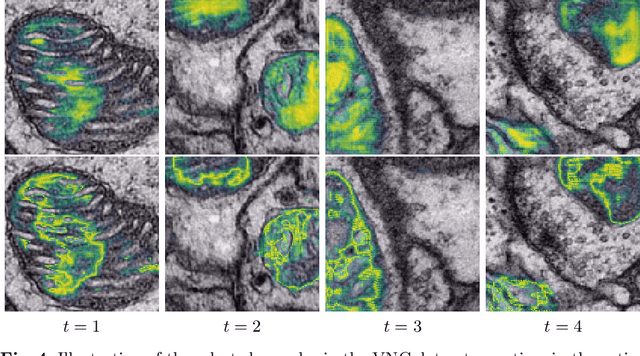

Abstract:In the last years, automated segmentation has become a necessary tool for volume electron microscopy (EM) imaging. So far, the best performing techniques have been largely based on fully supervised encoder-decoder CNNs, requiring a substantial amount of annotated images. Domain Adaptation (DA) aims to alleviate the annotation burden by 'adapting' the networks trained on existing groundtruth data (source domain) to work on a different (target) domain with as little additional annotation as possible. Most DA research is focused on the classification task, whereas volume EM segmentation remains rather unexplored. In this work, we extend recently proposed classification DA techniques to an encoder-decoder layout and propose a novel method that adds a reconstruction decoder to the classical encoder-decoder segmentation in order to align source and target encoder features. The method has been validated on the task of segmenting mitochondria in EM volumes. We have performed DA from brain EM images to HeLa cells and from isotropic FIB/SEM volumes to anisotropic TEM volumes. In all cases, the proposed method has outperformed the extended classification DA techniques and the finetuning baseline. An implementation of our work can be found on https://github.com/JorisRoels/domain-adaptive-segmentation.